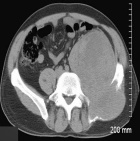

K.M. - 42 year old male c/o a sharp, moderate, constant pain in his lower back radiating down his LLE for four months. He reports some LLE weakness, which does not limit his ambulation. He has also noticed a bulge around his left pelvis. No F/C.

Zoom image: Radiological image Radiological image.